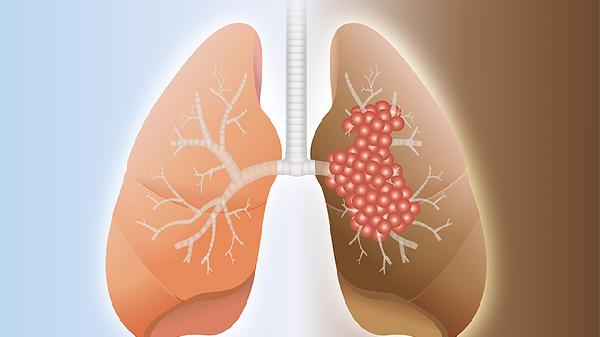

复方万年青胶囊对晚期肺癌可能有一定辅助作用,但需在医生指导下与其他治疗方案联合使用。该药物主要成分为中药提取物,具有扶正固本的功效,但晚期肺癌的治疗应以规范化的西医治疗为主。

复方万年青胶囊含有多种中药成分,可能通过调节免疫功能、减轻放化疗副作用等方式对晚期肺癌患者产生积极影响。部分临床观察显示,该药物可能有助于改善患者生活质量,减轻癌性疼痛等症状。但需注意中药起效较慢,不能替代手术、放疗、化疗等主要治疗手段。